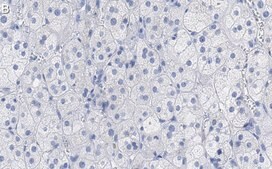

Western Blotting Analysis: A 1:1,000 dilution of this antibody detected SCARB1 in Human adrenal gland tissue lysate.Tested applicationsWestern Blotting Analysis: A 1:1,000 dilution from a representative lot detected SCARB1 in HeLa Membrane extract.Affinity Binding Assay: A representative lot of this antibody bound SCARB1 peptide with a KD of 5.8 x 10-9 in an affinity binding assay.Immunohistochemistry (Paraffin) Analysis: A 1:100 dilution from a representative lot detected SCARB1 in human adrenal gland tissue sections.Note: Actual optimal working dilutions must be determined by end user as specimens, and experimental conditions may vary with the end user